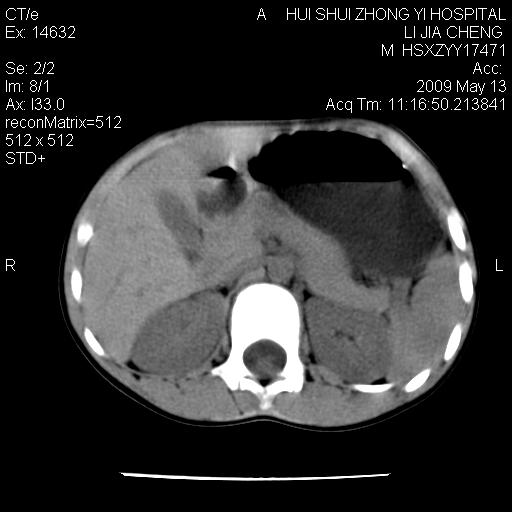

脂肪肉瘤可能性大,大血管边界不清,特别是腔静脉。不除外其他腹膜后肿瘤。

建议增强检查。

分不清楚,增强吧!!

建议增强。

建议增强进一步检查。